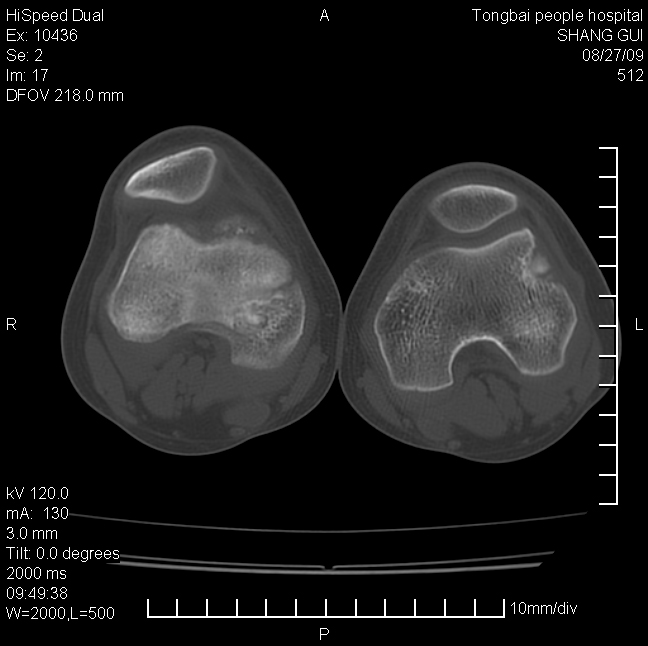

女,12岁。无意发现股骨下端隆起。局部皮肤颜色,温度无异常。

考虑右股骨下端骨纤维结构不良;不排除非骨化性纤维瘤。

不能排除,其实平片更直观。宽基底骨软骨瘤皮质与骨干皮质相连,髓腔与髓腔相通,骨纹理走行方向一致,部分软骨帽可有钙化,本例病变内“磨玻璃状、多囊状改变”比较符合骨纤。